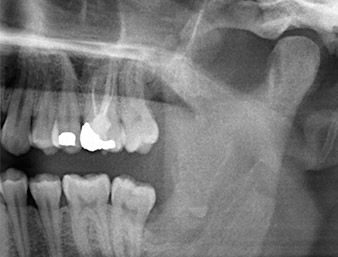

Der Wurzelrest regio 38 zeigte bereits in der Panoramaschichtaufnahme eine enge Lagebeziehung zum Nervus alveolaris inferior. (Abb. 1)

Unser Patient besaß anamnestisch gute Voraussetzungen (Nichtraucher, 26 Jahre) für einen erfolgreichen Eingriff. Wegen des Hinweises auf enge Lagebeziehung des Wurzelrestes zum N. alveolaris inferior in der Panoramaschicht-Aufnahme wurde zusätzlich eine digitale Volumentomografie erstellt (6).